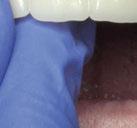

Este último aparato funcional se mantuvo en boca durante 8 meses, tras haber conseguido la mejoría esperada en cuanto al aspecto facial (figura 17) y las relaciones oclusales (figuras 18 a 22). La mordida abierta lateral producida es fácilmente solucionable en la siguiente fase de tratamiento.

(USS), como se aprecia en las figuras 23 a 25, comienza la segunda fase de tratamiento. Esta duró tan solo 12 meses debido a que gran parte de las relaciones oclusales habían mejorado durante la etapa anterior. Los resultados finales del tratamiento se observan en las figuras 26 a 30 , con la corrección de la clase molar y canina, el resalte y la sobremordida, el centrado de las líneas 1/2 y la curva de Spee. La mejoría en la macro, mini y microestética facial se aprecia en las figuras 31 a 33 , a pesar de la evidente desviación del mentón hacia